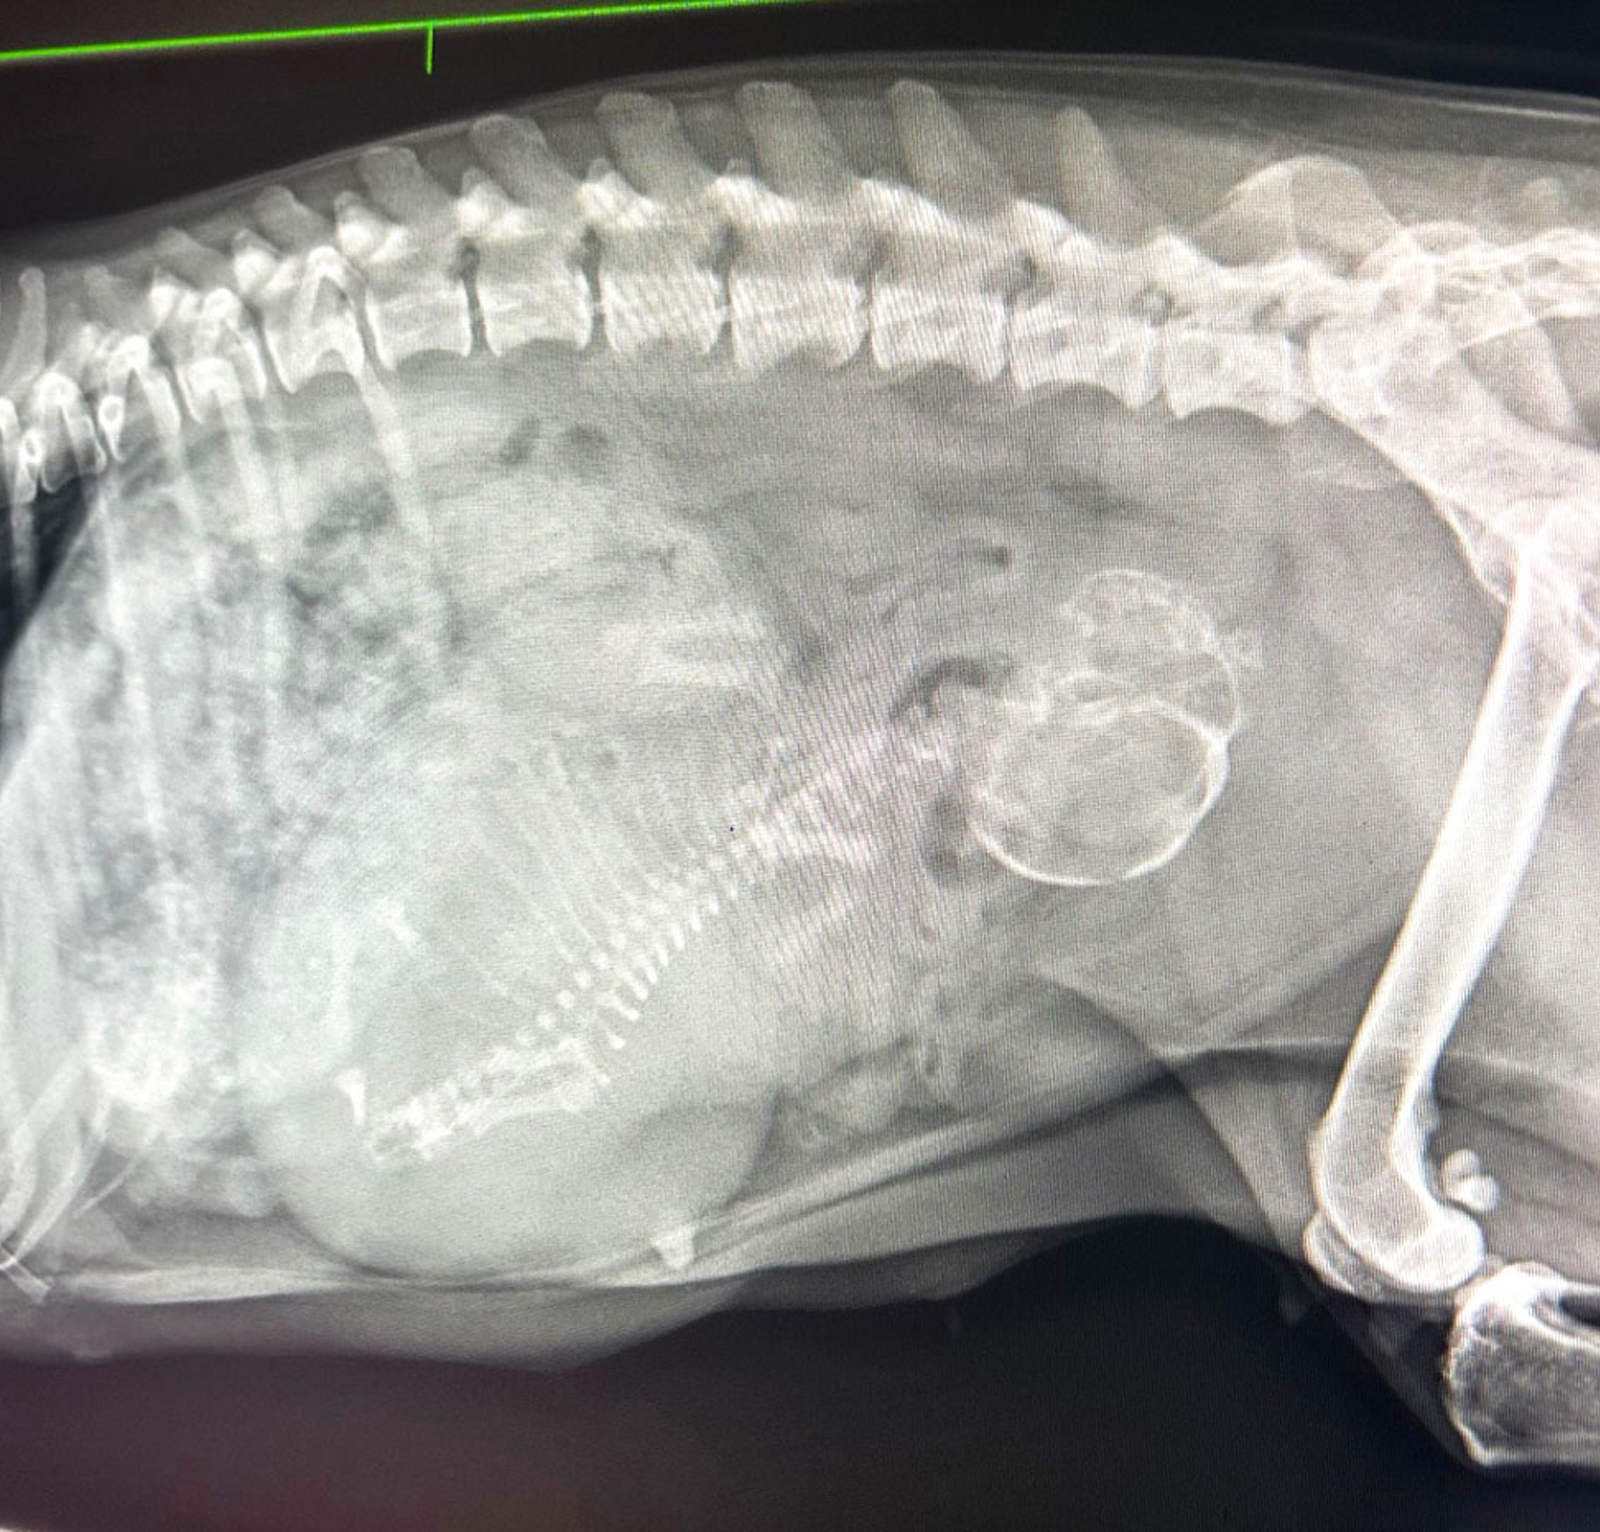

- X-rays (Radiography): Ideal for examining bones, joints, and organs, providing quick and clear snapshots of your pet’s internal structures.

- Ultrasound: Utilises sound waves to capture detailed images of soft tissues and organs, offering real-time insights into internal dynamics.